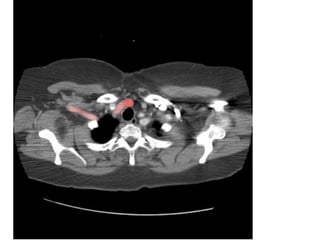

VỠ LOÉT ĐỘNG MẠCH CHỦ NGỰC

-> MÁU XOANG NGỰC (T)

VỠ LOÉT ĐỘNGMẠCH CHỦ NGỰC -> MÁU XOANG NGỰC (T)

HÌNH 2 1, Righthumeral head. 2, Oesophagus. 3, Trachea. 4, Left subclavian vein. 5, Scapular spine. 6, Glena October 31, 2014 13

• 115.